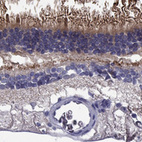

Immunohistochemical staining of human retina shows strong cytoplasmic positivity in photoreceptor cells.